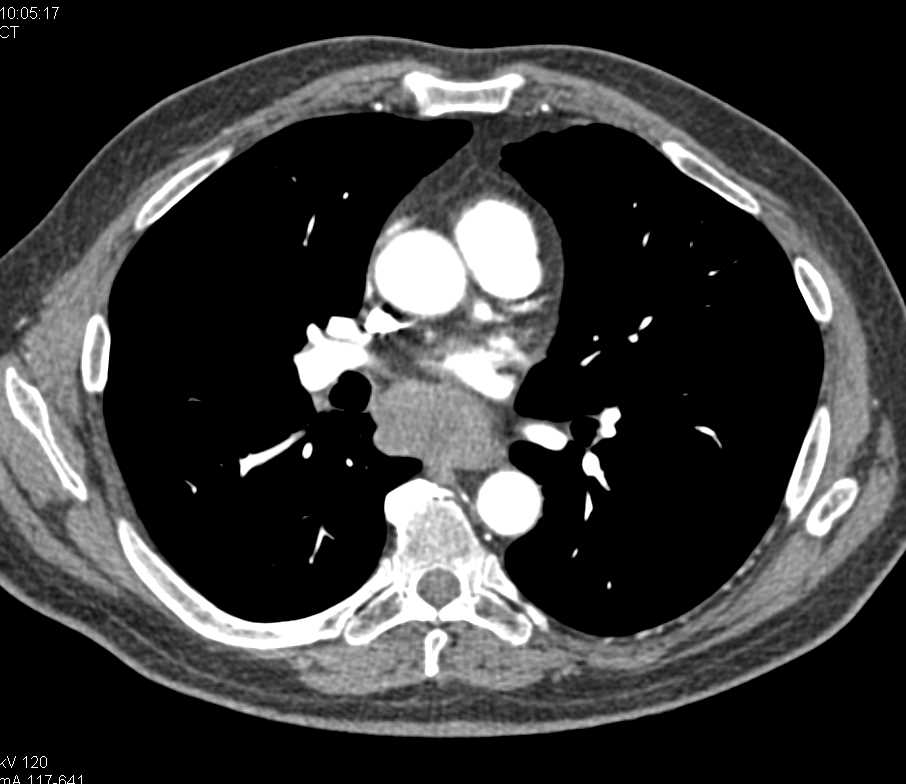

Emphysematous Gastritis with Collateral Vessels